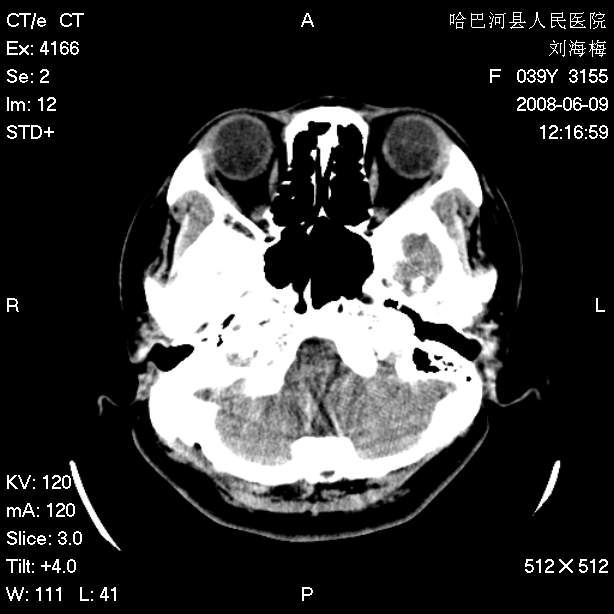

标题: CT13909:F39Y,头痛1年 [打印本页]

标题: CT13909:F39Y,头痛1年

头痛1年

枕骨蛛网膜颗粒压迹。

嗜酸性肉芽肿?骨髓瘤?不像蛛网膜颗粒压迹,太大了,并且有占位效应。

枕骨胆脂瘤

支持枕骨蛛网膜颗粒压迹。头痛与此无关。

1.应该考虑表皮样囊肿

2.右中耳乳突应薄扫!

支持枕骨胆脂瘤可能性最大。右侧乳突部密度增高,建议薄扫。